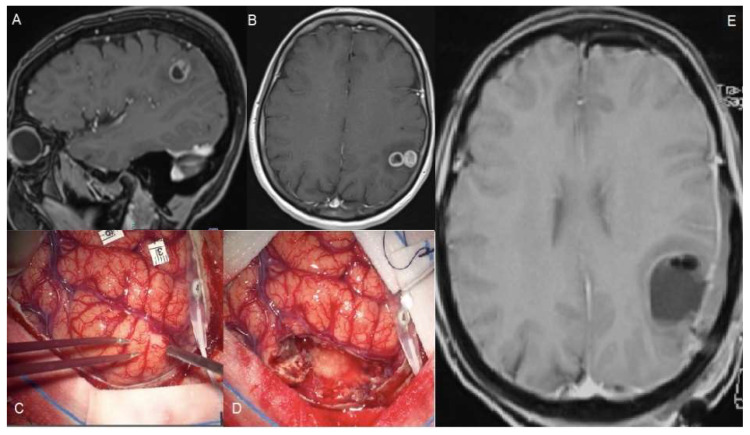

Glioblastoma are the most common primary malignant brain tumors with a highly infiltrative behavior. The extent of resection of the enhancing component has been shown to be correlated to survival. Recently, it has been proposed to move the resection beyond the contrast-enhanced portion into the MR hyper intense tissue which typically surrounds the tumor, the so-called supra marginal resection (SMR). Though it should be associated with better overall survival (OS), a potential harmful resection must be avoided in order not to create new neurological deficits. Through this work, we aimed to perform a critical review of SMR in patients with Glioblastoma. A Medline database search and a pooled meta-analysis of HRs were conducted; 19 articles were included. Meta-analysis revealed a pooled OS HR of 0.64 (p = 0.052). SMR is generally considered as the resection of any T1w gadolinium-enhanced tumor exceeding FLAIR volume, but no consensus exists about the amount of volume that must be resected to have an OS gain. Equally, the role and the weight of several pre-operative features (tumor volume, location, eloquence, etc.), the intraoperative methods to extend resection, and the post-operative deficits, need to be considered more deeply in future studies.